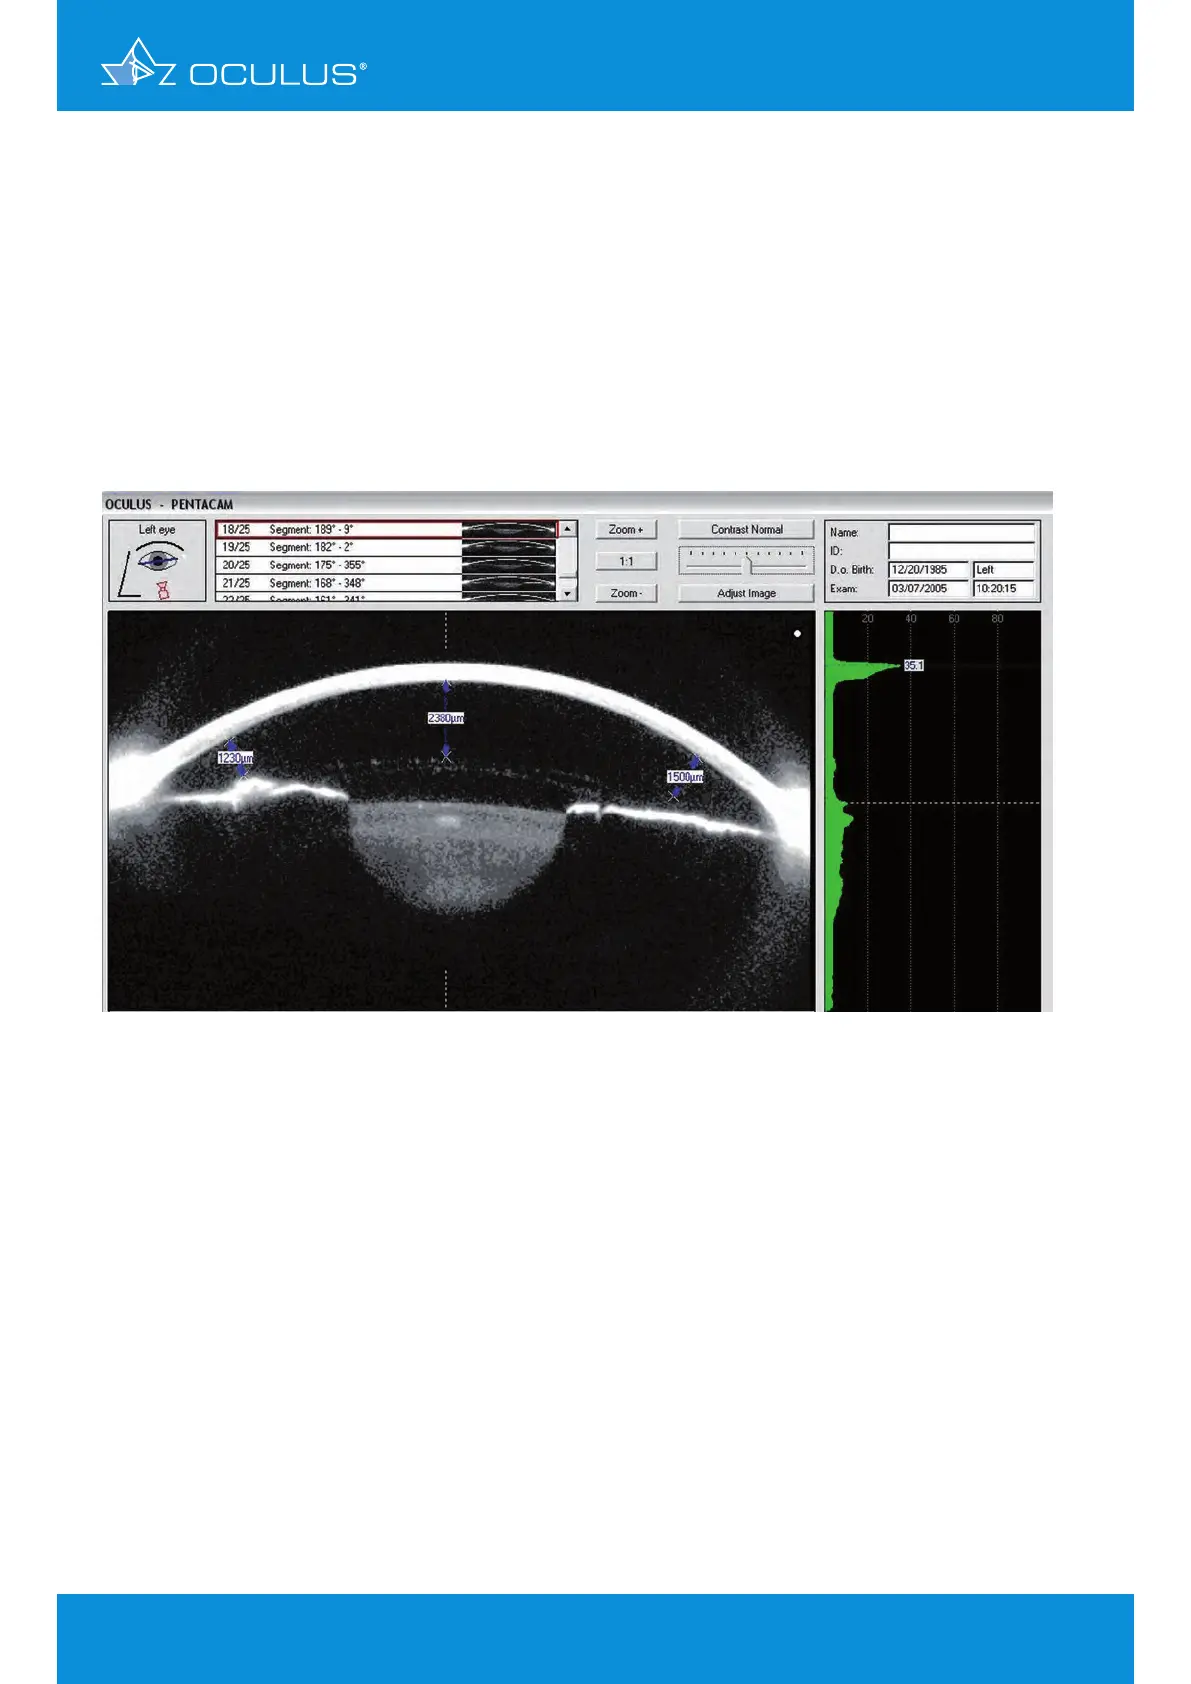

The Scheimpflug image shown below displays the same case after successful Artisan pIOL

implantation. It is evident there is space from the anterior pIOL surface to the endothelium centrally

and at the periphery (Figure 177). The posterior of the pIOL also has enough distance to the iris and

to the crystalline lens. Her post-op refraction:

Figure 177: Scheimpflug Image after Artisan IOL implantation